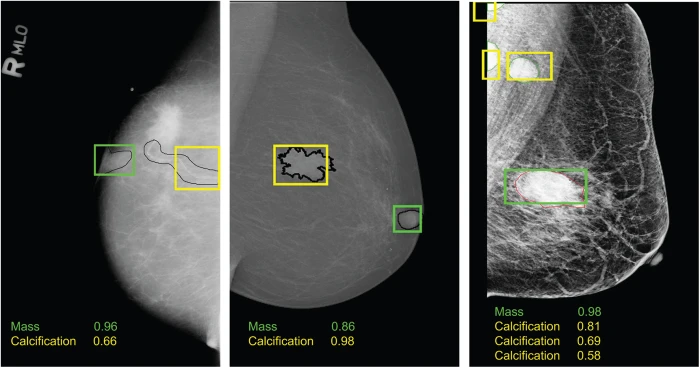

Artificial Intelligence in Mammography

AI algorithms are being developed to assist radiologists in interpreting mammograms. These tools have the potential to:

- Improve the accuracy of breast cancer detection

- Reduce the workload on radiologists

- Provide more consistent interpretations across different healthcare settings

How might AI change the future of mammography? While AI is not expected to replace human radiologists, it could serve as a powerful tool to enhance their capabilities, potentially leading to earlier detection of breast cancer and reduced false positives.